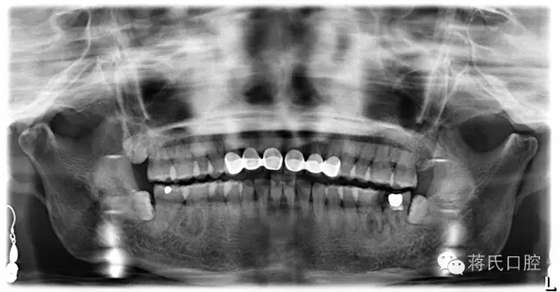

術(shù)前檢查:全景片顯示左下六七殘冠并發(fā)根尖炎癥,骨量豐滿、骨高度良好、但因?yàn)闅埞跁r間較長,對合牙伸長,咬合距離低,建議患者正畸治療上牙,但患者拒絕。因?yàn)榛颊呤墙處熉殬I(yè)所以在設(shè)計方案及治療溝通中詳細(xì)醫(yī)囑,每次治療均經(jīng)過患者同意后操作。

種植前全景片